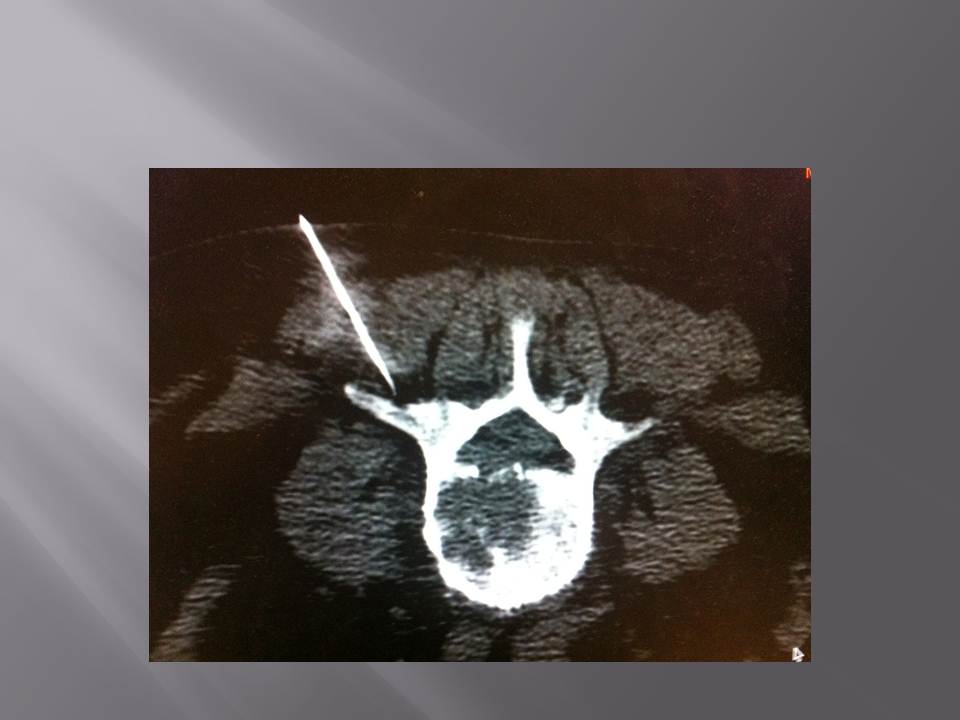

Biopsie sous guidage scanner